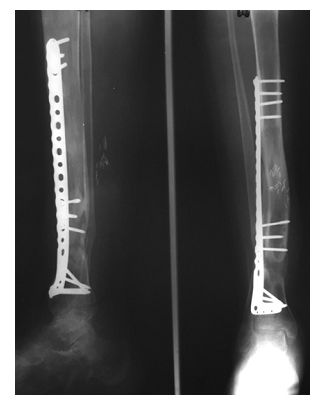

等确定感染控制了,软组织条件好了,行II期手术,本文作者介绍了一种组合式固定方式+骨搬运。

➤ 1、骨科外固定支架单边(用于骨搬运+支撑);

➤ 2、锁定长钢板(维持长度+支撑);

➤ 3、I期术后12个月,搬运到位后,直接上螺钉固定,去除外固定架。

I期术后2年,患者终于获得骨愈合。